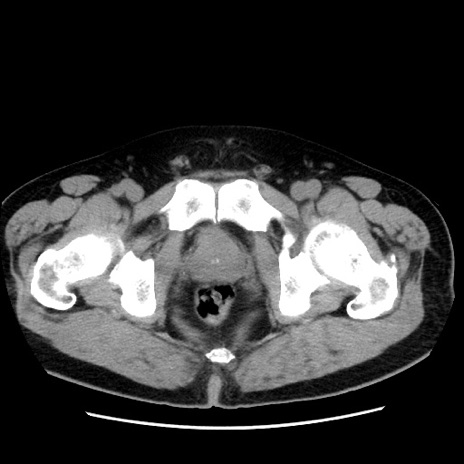

冠状断像

【症例】 70歳代男性

【主訴】 腹痛、嘔吐

【現病歴】 約1ヶ月前より間欠的に腹痛と嘔吐あり、当院消化器内科を受診したところCTで多発する肝臓のLDAを指摘され、精査中であった。以降は消化器症状は安定していたが、2日前より嘔気と腹痛があり、同日より排便・排ガスが消失した。改善認めず、 本日、救急外来を受診した。

【既往歴】 大腸ポリープ切除後。

【身体所見】意識清明・会話良好、BT 36.3℃、BP 127/80mmHg、 P 80bpm、腹部:膨満あり、平坦・軟、上腹部正中および下腹部正中に圧痛あり、反跳痛なし、筋性防御なし。

【データ】WBC 7200、CRP 0.77